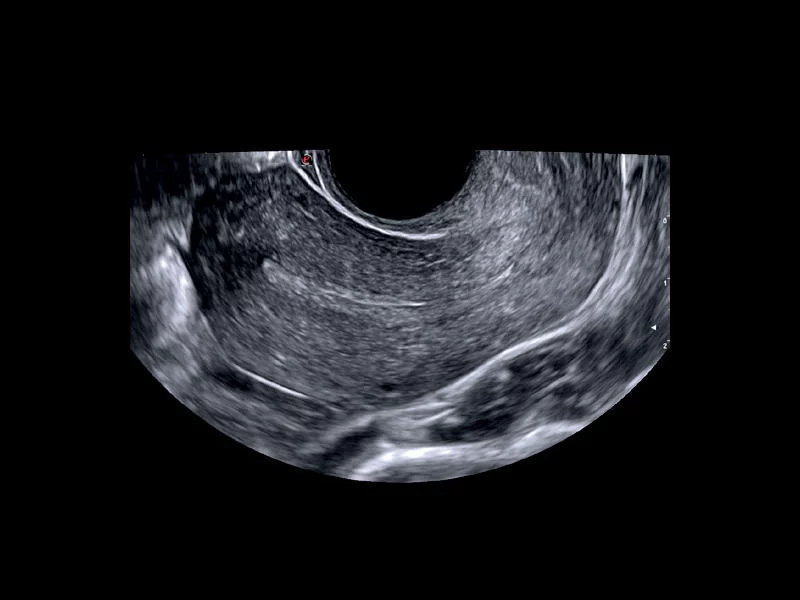

MyLab™E80 - Power Doppler - Gynaecology

MyLab™E80 - Power Doppler - Gynaecology